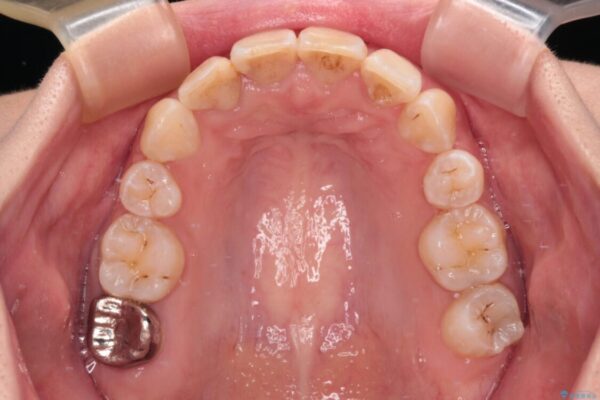

治療後

• デコボコと深い咬み合わせ ワイヤー装置での抜歯矯正 治療後画像